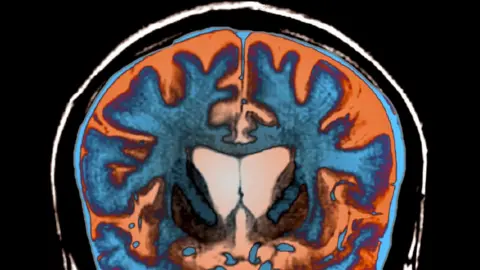

Volunteers had several tests over three years, including brain scans and clinical check-ups to see how Huntington's disease affected people's thinking skills and movement as the condition became more severe.